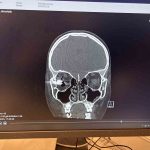

Özbekistan uyruklu 10 yaşındaki Ahrorbek Hojimurodov, Aralık 2025 tarihinde evde kuzeni ile birlikte silahla oynamaya başladı. Babası Bunyodjon Imomov’un uyarılarına rağmen çocukların oynadıkları silah bir anda patladı. Patlamanın etkisiyle silahtan çıkan mermi, Hojimurodov’un sağ gözüne çok yakın bir bölgeden beynine isabet etti. Babası tarafından ilk olarak Taşkent’teki bir hastaneye götürülen ve gözünü kaybetme riski bulunan Hojimurodov’a başarı oranı yüzde 40-60 olarak verildi. Bunun üzerine baba Imomov, oğlunu tedavi için Türkiye’ye getirerek Memorial Ataşehir Hastanesi’ndeki doktorlara teslim etti. Göz, plastik cerrahi ve beyin cerrahisi bölümlerinin koordineli çalışmalarıyla birlikte Hojimurodov’un ameliyatı başarıyla tamamlandı. Memorial Ataşehir Hastanesi Beyin ve Sinir Cerrahisi Bölümü’nden Prof. Dr. Zafer Orkun Toktaş, Hojimurodov’un tedavisinde kullanılan ve klasik yöntemlerden farklı olarak kapalı şekilde; adeta ’askeri dron sistemi’ne benzer yöntemlerle gerçekleştirilen ’Nöronavigasyon’ teknolojili operasyonun detaylarını aktardı.

“Gerçekten bizim için unutulmazlardan biri oldu bu hastamız çünkü hem olayın oluş şekli hem de bize geliş şekli üzücüydü. Kuzeniyle oynarken bir silah yaralanması oluyor ve beyne son anda girmekten kurtulan ama maalesef göze doğru yönelen bir mermi vardı. Bu hasta bize yurtdışından ulaştı. Tabii ki biraz da teknoloji için ulaştığını düşünüyoruz çünkü gerçekten teknolojiye ihtiyacımız olan bir vakaydı. Bu vakada hem göz ekibi, hem plastik cerrahi ekibi hem de beyin cerrahisi ekibi ortak bir çalışma yaptı. Eski klasik yöntemlerde olduğu gibi biz bu hastada kafatasını açmadık. Ameliyatı gözden küçük bir kesi ile girerek gerçekleştirdik. Gözün dış duvarından navigasyon teknolojisiyle sadece 2 santimlik bir kesi yapılarak; yani halk arasında ’kapalı’ olarak bilinen yöntemle çalıştık. Kemikte sadece merminin boyu kadar bir delik açarak bu mermi çıkartılmış oldu. Sonrasında hasta göz bölümüne devredildi, tamamen oranın takibi ve kontrolü altında şu anda ve sanıyorum ki o gözün görmesi de kurtarılacak, beklentilerimiz ve dileklerimiz bu yönde. Elbette ki çocuğumuzun hayatının kurtulması da bizim için ayrı bir sevinç kaynağı.”